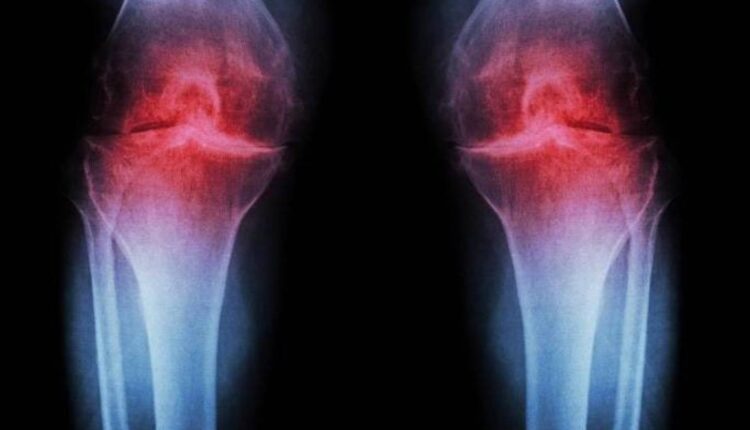

علاج تجريبي يعيد إنماء غضروف الركبة ويوقف تطوّر التهاب المفاصل

كشفت دراسة حديثة أجراها باحثون في جامعة ستانفورد للطب عن علاج تجريبي مبتكر قادر على إعادة إنماء غضروف الركبة المتضرّر بفعل التقدّم في العمر أو الإصابات، وذلك عبر إعادة برمجة الخلايا الغضروفية الموجودة داخل المفصل من دون الحاجة إلى الخلايا الجذعية.

وأظهرت التجارب أنّ العلاج، الذي يعمل على تعطيل بروتين مرتبط بالشيخوخة، نجح في إعادة بناء الغضروف المتآكل في مفاصل فئران مسنّة، كما أوقف تطوّر التهاب المفاصل بعد إصابات مشابهة لتمزّق الرباط الصليبي الأمامي، وهي من الإصابات الشائعة لدى الرياضيين والأشخاص النشطين.

ولم يقتصر تأثير العلاج القابل للحقن على إعادة بناء الغضروف فحسب، بل أثبت أيضًا قدرته على منع تطوّر التهاب المفاصل بعد الإصابة. كما تخضع نسخة فموية من العلاج لتجارب سريرية تستهدف علاج ضعف العضلات المرتبط بالتقدّم في العمر.

وفي خطوة واعدة، استجابت أنسجة ركبة بشرية جرى الحصول عليها خلال عمليات استبدال المفاصل بشكل إيجابي للعلاج، حيث بدأت الخلايا الغضروفية والمصفوفة خارج الخلوية بتكوين غضروف جديد يعمل بصورة طبيعية.